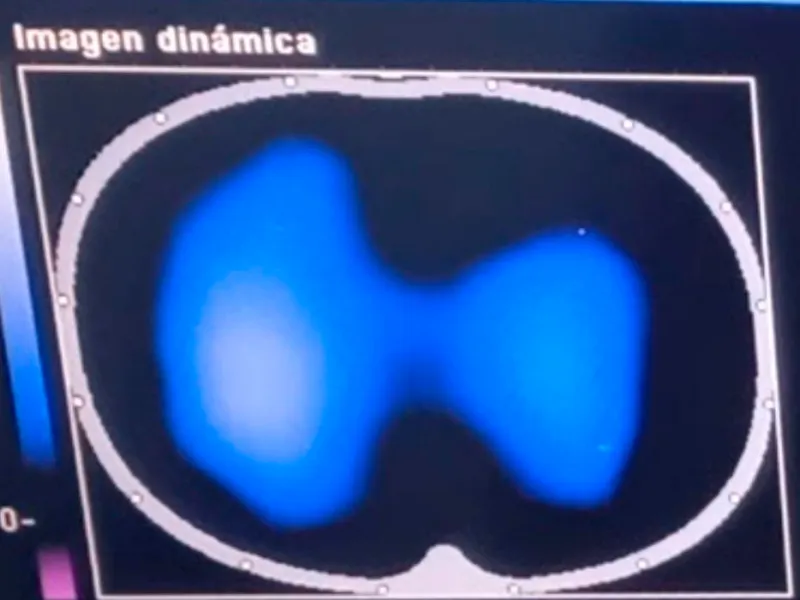

Imágenes de tomografía que se toman para analizar el desempeño de la fisioterapia con el incentivo de re-expansión pulmonar. El área de color azul-blanco representa el volumen del pulmón en un corte transversal, visto desde arriba, cuanto mayor aire llega a los pulmones se expande el pulmón y llega aire a zonas al pulmón que originalmente no se utilizaban.

Imágenes de tomografía que se toman para analizar el desempeño de la fisioterapia con el incentivo de re-expansión pulmonar. El área de color azul-blanco representa el volumen del pulmón en un corte transversal, visto desde arriba, cuanto mayor aire llega a los pulmones se expande el pulmón y llega aire a zonas al pulmón que originalmente no se utilizaban.

Imágenes de tomografía que se toman para analizar el desempeño de la fisioterapia con el incentivo de re-expansión pulmonar. El área de color azul-blanco representa el volumen del pulmón en un corte transversal, visto desde arriba, cuanto mayor aire llega a los pulmones se expande el pulmón y llega aire a zonas al pulmón que originalmente no se utilizaban.